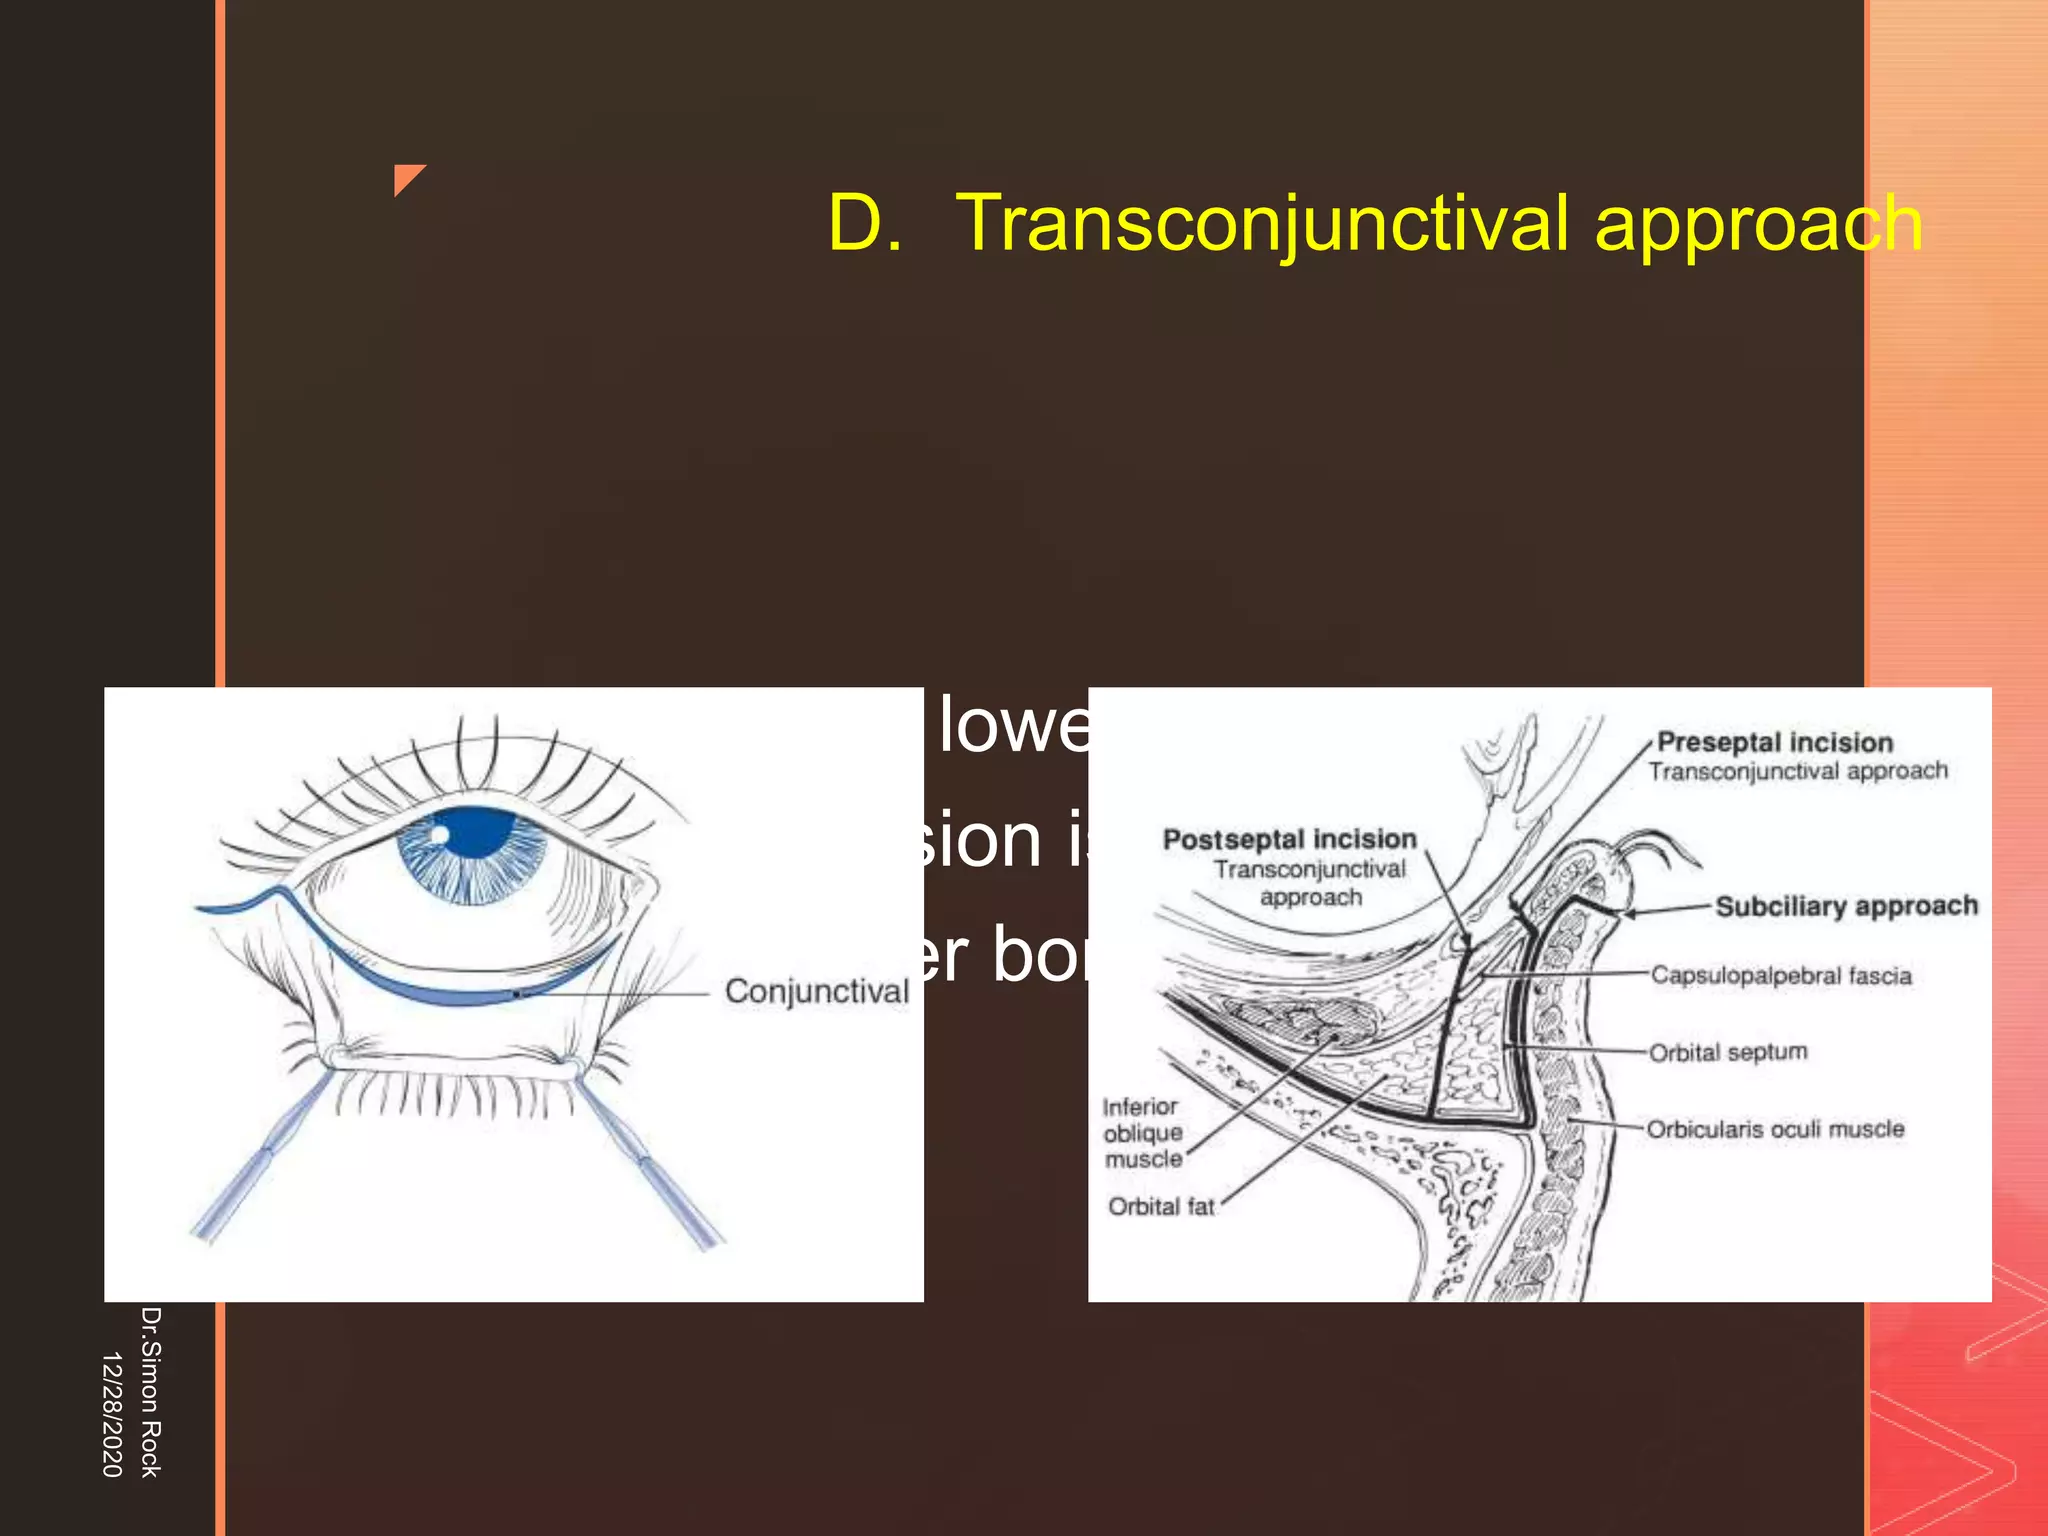

This document discusses the anatomy and fractures of the zygomatic bone. It notes that the zygoma forms the cheekbone and articulates with several other facial bones. Zygomatic fractures most commonly occur in the arch or body due to blunt trauma. Diagnosis involves checking for diplopia, ecchymosis, and other signs of orbital or facial bone involvement. Treatment may involve closed or open reduction based on the severity of displacement. Closed reduction techniques try to elevate the bone back into position without surgery, while open reduction requires surgical exposure and fixation of the fracture site.